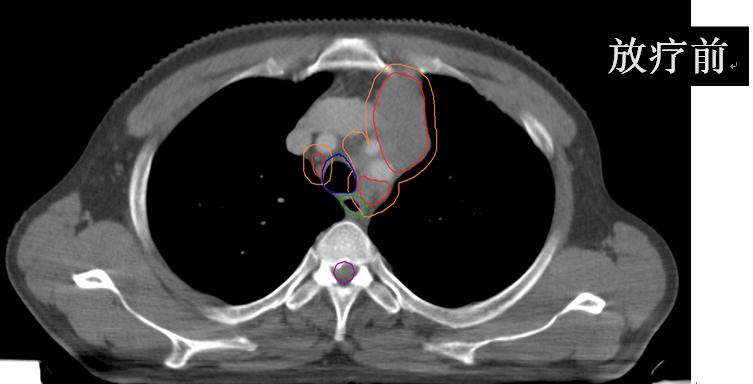

• (肺及纵隔病灶)iGTV1/GTV1/CTV1/70Gy/60Gy/50Gy/20F;

• (锁骨上病灶)GTV2/CTV2/60Gy/50Gy/20F。

放疗后患者咳嗽、咳痰、左肩背部疼痛、痰中带血、胸闷、气短完全缓解;继续于外院行综合治疗并定期随访观察。

有图有真相:放疗效果显著!是不是疗效好就应该损伤重呢?肺损伤?